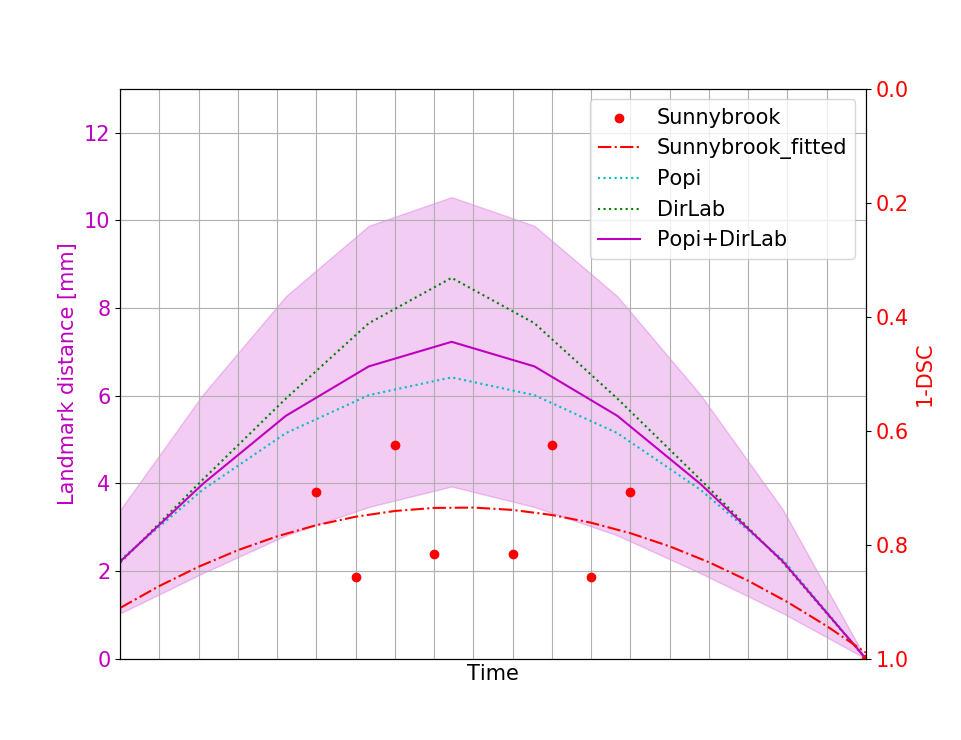

The initial average landmark distance between consecutive phase images was 2.25 1.55 mm for the Popi datasets and 2.19 2.02 mm for the DirLab datasets. The proposed registration algorithm could decrease the average distance to 1.24 0.90 mm and 1.54 1.31 mm, respectively. For a comparison with existing 4D registration methods we applied the publicly available method by [23] to the respiratory datasets and achieved average registration errors similar to the ones of our method: 1.56 1.42 mm for the DirLab and 1.11 0.87 mm for the Popi datasets. The construction of trajectories for voxels requires the combination of all DVF of a 4D dataset. As a consequence the registration error at the start of a trajectory gets propagated over time and increases or decreases with the combination of the different DVF. In Fig. 4 the error evolution is visualised for the three test datasets. At the beginning the mean registration error is 1.54 mm for the DirLab datasets and 1.24 mm for the Popi datasets. The error then increases to a mean of 2.58 mm for DirLab and 2.07 mm for Popi in the middle of the periodic motion. In the end of the breathing cycle the error falls to an error around 1 mm for both datasets. A similar error propagation pattern could be measured for the Sunnybrook datasets. For the Sunnybrook datasets segmentations are only available for the extreme phases, which allows only four comparisons per dataset. When starting with the end-diastolic phase a comparison in the middle of the cyclic motion to the end-systolic segmentation and in the end of the cycle motion to the original end-diastolic segmentation is possible. The same applies when starting with the end-systolic segmentation. In Fig. 4 the red dots indicate the measured DSC overlap, the red dotted line was fitted to the dots and estimates the DSC overlap for phase images without a segmentation available. Compared to a direct registration of the maximum exhale and inhale phases the registration error increased on average by 0.48 mm with the combination of the DVF. The average registration error for the extreme phases in the Popi dataset increased from 1.46 1.59 mm to 1.98 1.56 mm when we registered the whole 4D dataset instead of the two extreme phases solely. The same analysis reported an increase from 1.83 2.35 mm to 2.54 2.01 mm for the DirLab images and and decrease in the DSC from 0.86 0.10 to 0.79 0.14 for the Sunnybrook data. The DVF of the 4D evaluation showed a FoF of 0.02 % and an average Jacobi determinant of 1.00 0.06.

V-D Downsampling And Few Shot Learning

When we used only the first two layers of our network for registration the performance decreased slightly but the gain in computation time was huge. The average registration error for registering 3D respiratory images was 1.84 1.88 mm compared to 1.70 2.15 mm with all 3 layers. The computation time for two 3D images was on average 4 minutes, for 4D datasets the average time needed for registration increased to 8 minutes. The peak in error propagation increased to an average value of 2.32 1.55 mm, 3.08 2.27 mm and 0.75 0.14 DSC for the Popi, DirLab and Sunnybrook datasets, respectively. The few shot analysis on the DirLab dataset worked only for a setting with two downsampling layers. Training the third layer always resulted in an increase of the registration error for the dataset to be registered. Which is an indication that the network could not learn a general representation of detailed deformation from the limited amount of training data. Downsampling layer 1 and 2 were trained for 200 and 250 epochs, respectively. Applying the trained 2 layer models to the test data resulted in an registration error of 4.43 2.94 mm, but by fine tuning the model for 50 epochs the registration error could be decreased to 2.16 2.20 mm, which is comparable to the registration error of the one shot approach with 2.00 2.03 mm for the DirLab dataset and 2 layers. With the few shot approach the computation time could be reduced by a factor of 4 to 1 minute.